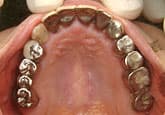

- 不適切な修復物:過去の不適切な歯科治療によって、ぴったりあっていない修復物を装着していると、歯肉との境が清掃不良となり、歯周病を憎悪させる要因となります。

- はぎしりや歯列不正:はぎしりによって歯に強い力がかかりつづけたり、歯列不正によって特定の歯だけが強く咬んでいると、歯周病を二次的に憎悪させる原因となります。もちろん、歯並びが悪いと清掃しにくくなり、歯周病を悪化させます。